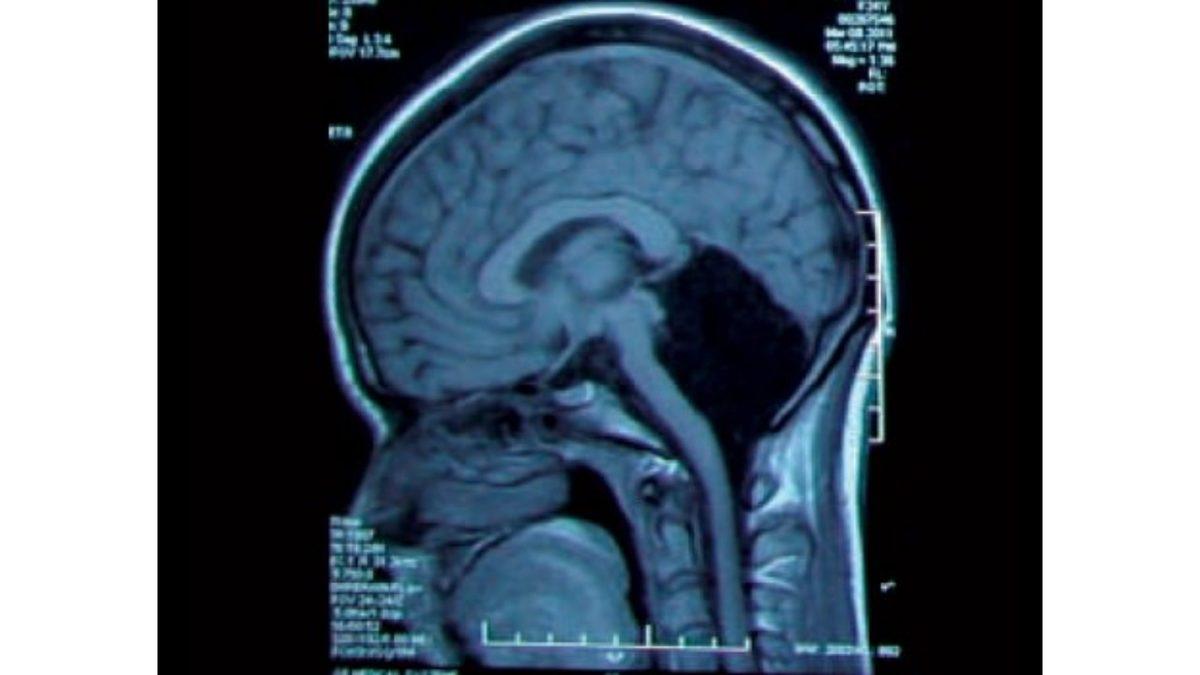

Jonathan, bir beyinciği olmadan doğmuştu ve beyinciğinin olması gereken yerde siyah bir boşluk vardı.

Mide bulantısı ve baş dönmesi şikayetleriyle doktora giden ve bu rahatsızlıklar ışığında tetkikleri yapılan kadının, 2014’te doktorlar tarafından beyinciğinin olmadığı ve bu organ yerine o bölgenin beyin omurilik sıvısıyla dolu olduğu tespit edildi.

Doktorlar eksik beyinciği, beynin diğer bölümlerinin devraldığını ve beyinciğin kaybolmasına sebep olan şeyin, aslında beynin “duruma uyum sağlaması” olarak ifade etti.